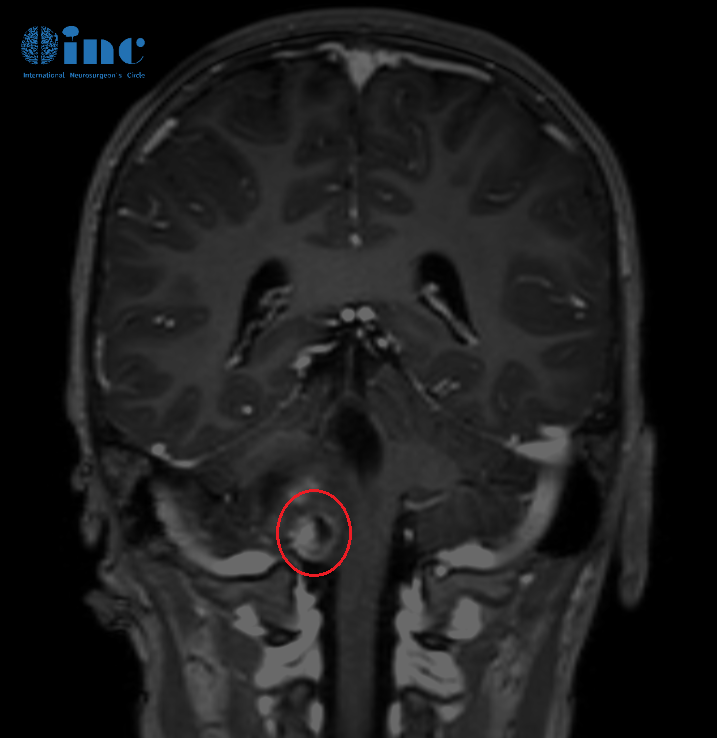

术前核磁影像

2022年08月25,常规核磁复查,结果提示肿瘤进展,延髓右部不规则肿胀范围约2.6cmX2.5cmX2.3cm。

▼天天术前术后影像对比图片